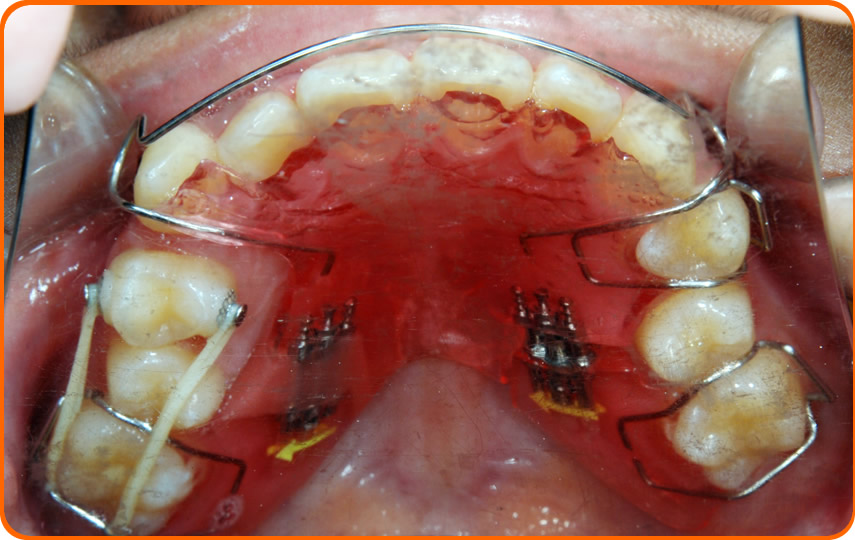

下に床矯正装置を装着

床矯正装置を装着

赤丸のネジを回して広げ、犬歯から奥の歯を移動し犬歯の入るスペースを作ります。

空いたスペースにゴムで引っ張って犬歯の入るスペースを作ります。

舌上下に床矯正装置を装着。